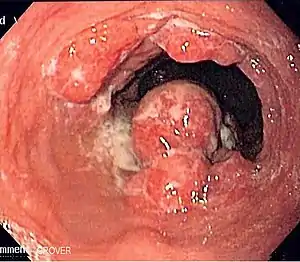

Cancers of the mouth, esophagus, pharynx, and larynx

Alcohol consumption at any quantity is a risk factor for cancers of the mouth, esophagus, pharynx and larynx. The U.S. National Cancer Institute states "Drinking alcohol increases the risk of cancers of the mouth, esophagus, pharynx, larynx, and liver in men and women, … In general, risks increases above baseline with any alcohol intake (mild; <2 glass of wine per week) and increases significantly with moderate alcohol intake (one glass of wine per day) with highest risk in those with greater than 7 glasses of wine per week. (A drink is defined as 12 ounces of regular beer, 5 ounces of wine, or 1.5 ounces of 80-proof liquor.) … Also, using alcohol with tobacco is riskier than using either one alone, because it further increases the chances of getting cancers of the mouth, throat, and esophagus."[41] The federal government's Dietary Guidelines for Americans 2010 defines moderate alcohol drinking as up to one drink per day for women and up to two drinks per day for men. Heavy alcohol drinking is defined as having more than three drinks on any day or more than seven drinks per week for women and more than four drinks on any day or more than 14 drinks per week for men.

The International Head and Neck Cancer Epidemiology (INHANCE) Consortium co-ordinated a meta-study on the issue.[42] A study looking at laryngeal cancer and beverage type concluded, "This study thus indicates that in the Italian population characterized by frequent wine consumption, wine is the beverage most strongly related to the risk of laryngeal cancer."[43]

A review of the epidemiological literature published from 1966 to 2006 concluded that:

- The risk of esophageal cancer nearly doubled in the first two years following alcohol cessation, a sharp increase that may be due to the fact that some people only stop drinking when they are already experiencing disease symptoms. However, risk then decreased rapidly and significantly after longer periods of abstention.

- Risk of head and neck cancer only reduced significantly after 10 years of cessation.

- After more than 20 years of alcohol cessation, the risks for both cancers were similar to those seen in people who never drank alcohol.[44][45]

A study concluded that for every additional drink regularly consumed per day, the incidence of oral cavity and pharynx cancers increases by 1 per 1000. The incidence of cancers of the esophagus and larynx increase by 0.7 per 1000.[40]

A 2008 study suggests that acetaldehyde (a breakdown product of alcohol) is implicated in oral cancer.[46][47]